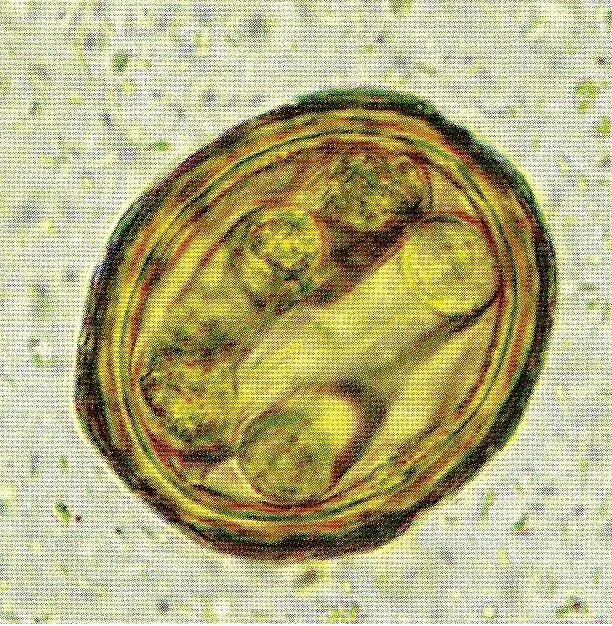

Личинка аскариды развивается в воде